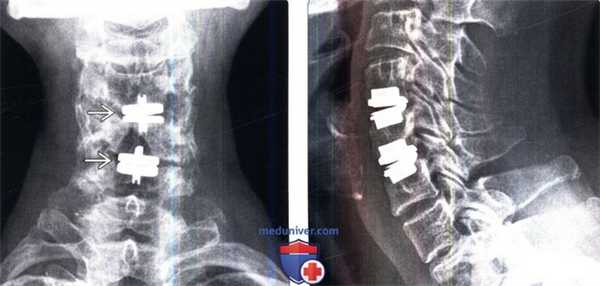

(Слева) Рентгенография шейного отдела позвоночника в боковой проекции: случай корпорэктомии С4 с замещением тела позвонка кейджем и стабилизацией С3-С5 сегмента вентральной пластиной. Подобные сетчатые кейджи выбираются исходя из размеров замыкательных пластинок и высоты дефекта. На этом снимке видны признаки некоторого коллапса тела С5 с проседанием в дефект пластины и кейджа.

(Справа) На рентгенограмме в прямой проекции и фронтальном КТ-срезе визуализируются парные кейджи Pyramesh, использованные для реконструкции коллабированного тела L2 позвонка. Вокруг кейджей визуализируется метилметакрилат.